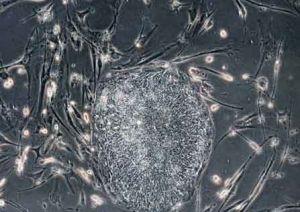

萬能細胞萬能細胞,美國和日本的研究小組宣布成功把普通的人體皮膚細胞轉化為了具備胚胎幹細胞功能的新型“萬能細胞”,是從人體中提取了一種名為“纖維原細胞”的皮膚細胞,然後向其中植入4種新基因,從而製造出一種名為IPS的細胞,它具有類似胚胎幹細胞的功能,能夠最終培育成人體組織或器官,這一被學界稱為生物科學“里程碑”的重大突破,有望幫助科學家繞過克隆技術的倫理、道德紛爭,為醫學套用打開大門。

1、研究小組都利用了相同的技術——基因重新編排技術,即向皮膚細胞中植入一組4個基因,通過基因重新編排,使皮膚細胞具備胚胎幹細胞的功能。這種被改造過的細胞稱作iPS細胞,研究小組選擇的植入基因組合略有不同,另外它們選用了不同類型的人體皮膚細胞為“底版”。山中伸彌研究小組從一名36歲女性的臉部提取了科學家稱為“纖維原細胞”的皮膚細胞。詹姆斯·湯姆森實驗室的皮膚細胞則是“成纖維細胞”,來自一名新生兒的陰莖包皮。

3、得出的實驗結果一樣——他們都成功地將普通人體皮膚細胞改造成了幹細胞。從理論上說這種幹細胞的功能類似通過胚胎克隆技術取得的胚胎幹細胞,能夠最終培育成人體組織或器官。由於這種幹細胞能通過基因組合控制,因此有“萬能細胞”、“變色龍細胞”之稱。